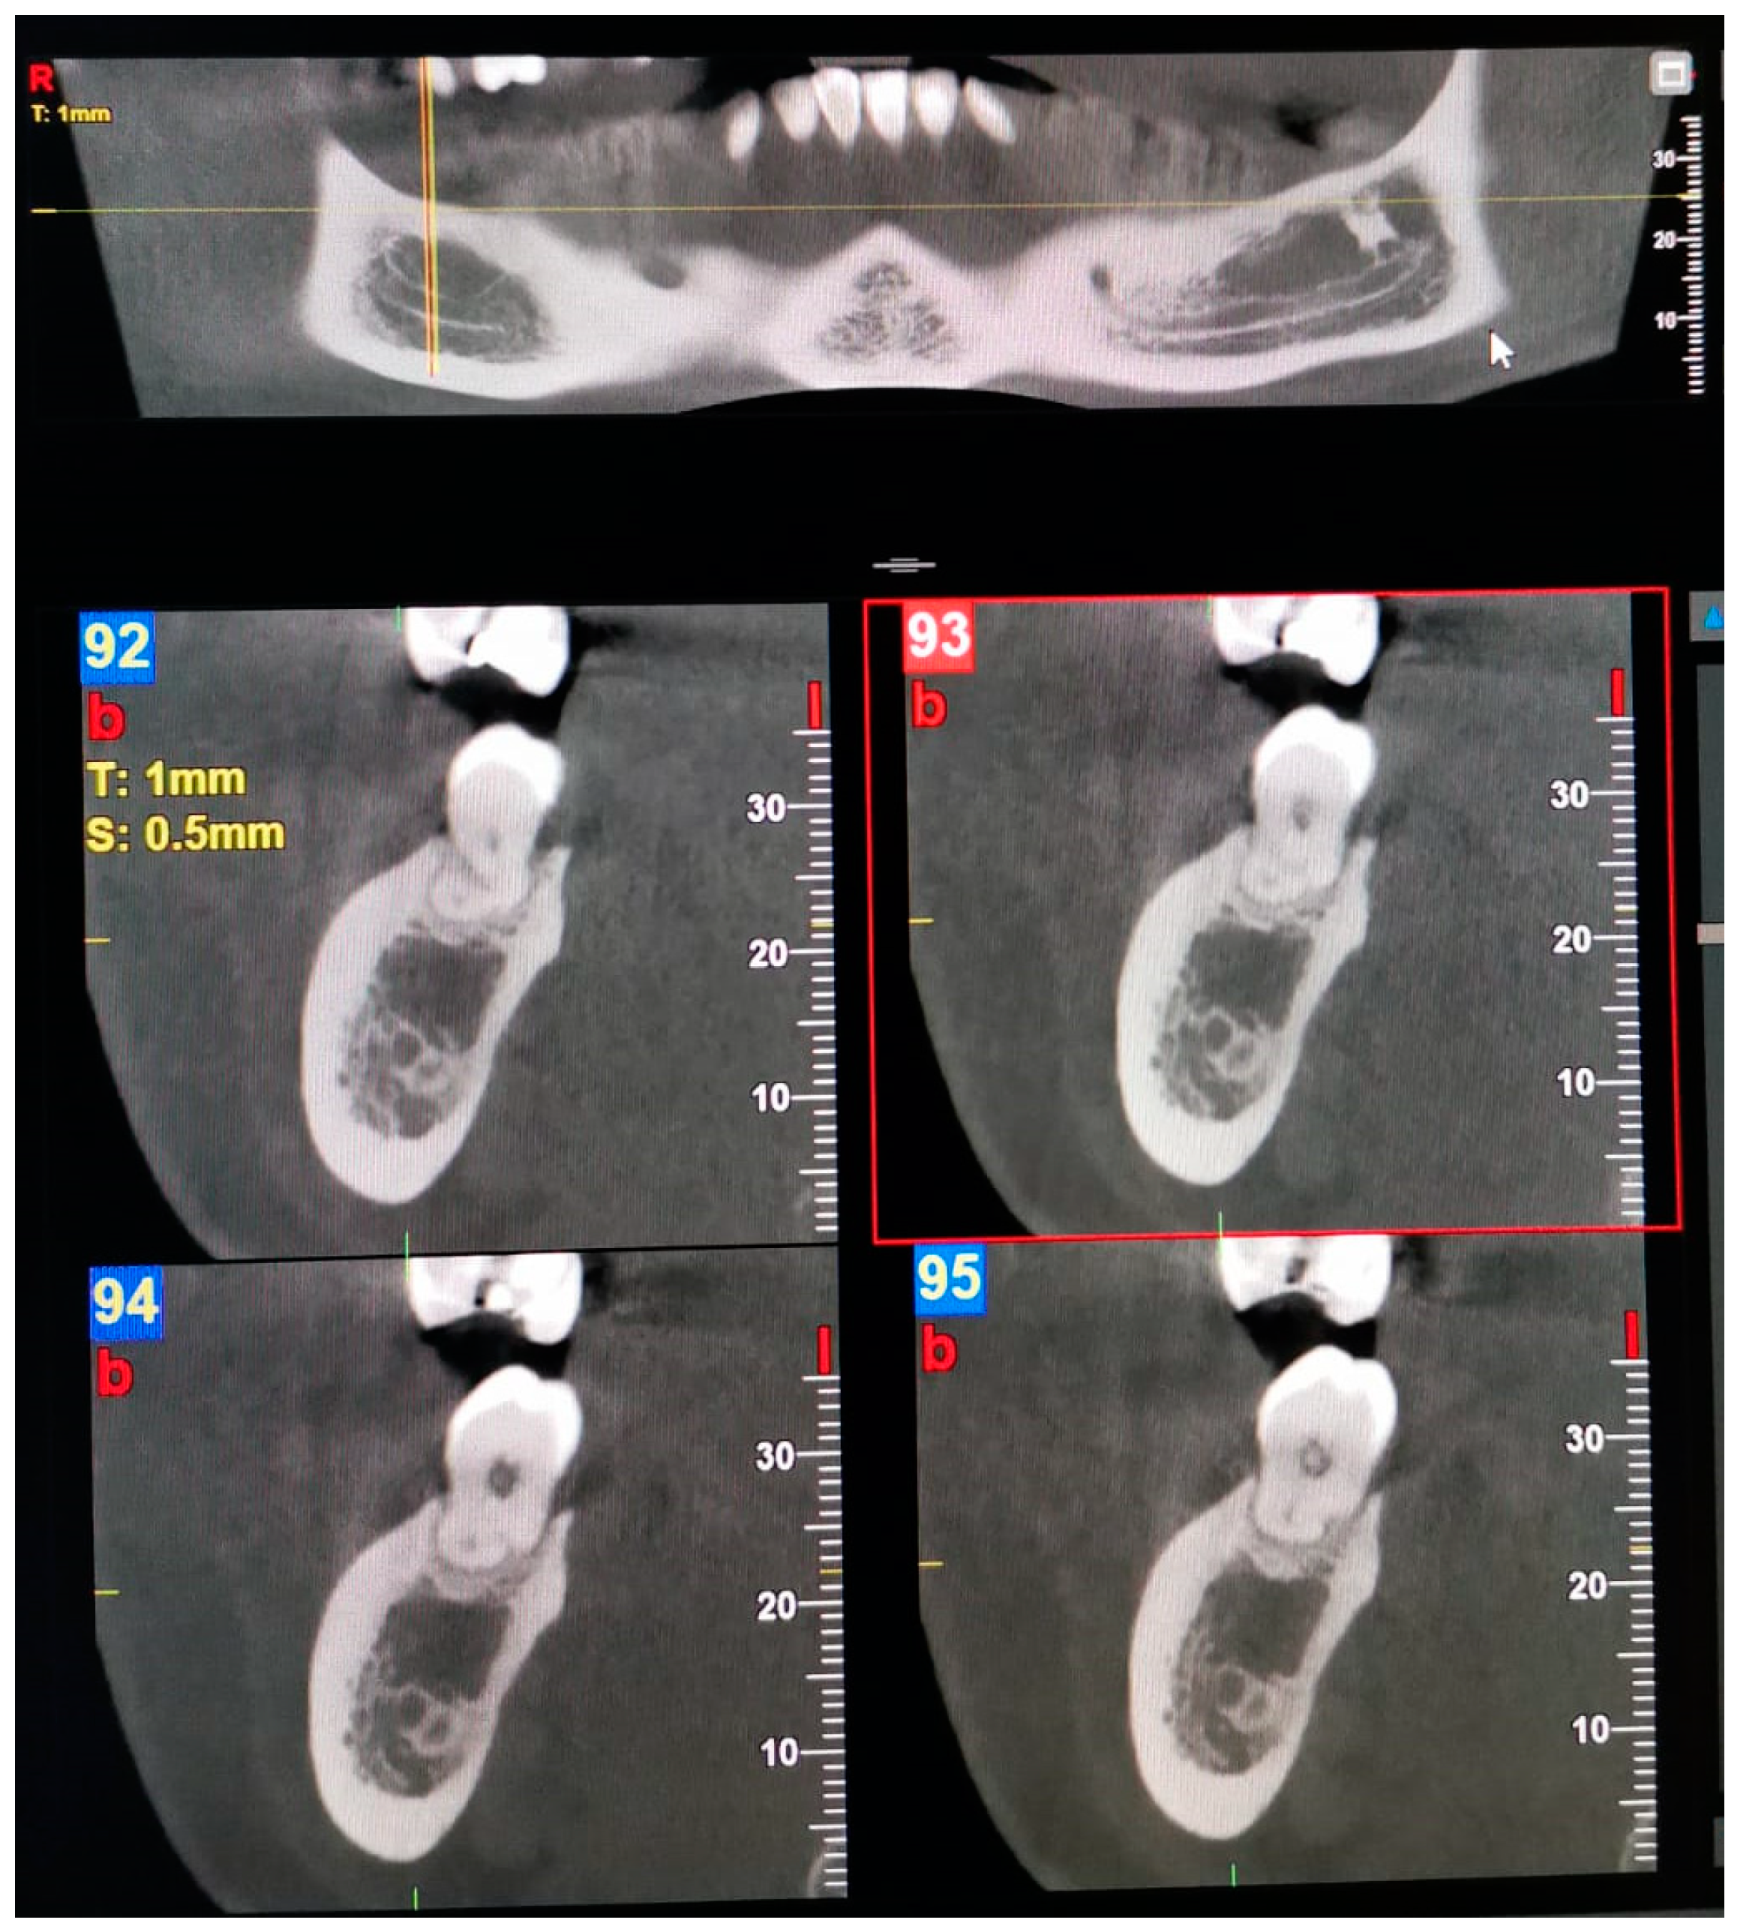

| 4—Buccolingual | The buccal canal, which bifurcates from the mandibular canal in the mandibular ramus, courses bucco-inferiorly.  Lingual canal: The lingual canal, which bifurcates from the mandibular canal in the mandibular ramus, courses lingually and then penetrates through the lingual cortical bone.  |